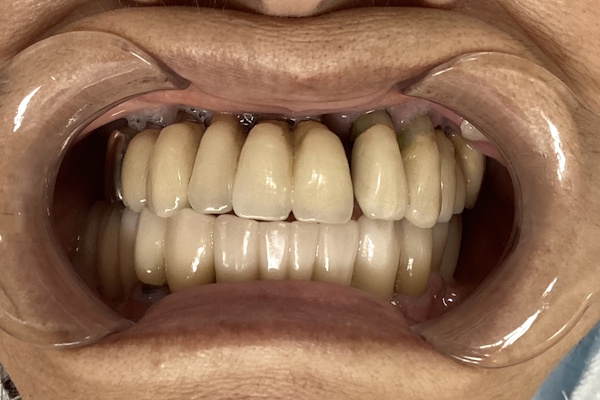

実際の見た目の写真

「下の入れ歯が合わない」ということでご来院いただきました。インプラント治療で快適に噛めるようになりました。

・治療:インプラント治療

・年齢:70代女性

・主訴:下の入れ歯が合わない。

・期間:1年(段階的にやったので期間はかかりました)

・回数:実質15回程度

・費用:300万円

・メリット:自分の歯のように噛める

・リスクと副作用:自由診療となる/術後の腫れや痛みを伴うことがある/その他